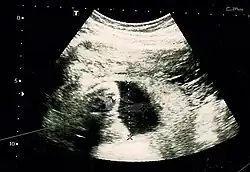

Image by Dahab AA, Aburass R, Shawkat W, Babgi R, Essa O, Mujallid RH

Suspicion of an abdominal pregnancy is raised when the baby‘s parts can be easily felt, or the lie is abnormal, the cervix is displaced, or there is failed induction of labor.[4] X-rays can be used to aid diagnosis.[9]